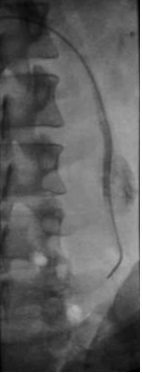

患者处于反Trendelenburg位置,进行左肾静脉造影,以发现睾丸静脉的返流。将导管插入左肾静脉,进行睾丸静脉造影以发现睾丸静脉的返流,以及体循环和门静脉系统的分支显像。使用护罩或充分的平行光,来尽量减少睾丸的暴露。无需对静索静脉曲张直接照相,这样可能会增加性腺接受的放射性剂量。导管进入腹股沟管的部位,因此应避免经阴囊照相。在试图阻断所有可能会引起复发的分支时,推荐使用5-mm和8-mm Gianturco圈(Cook, Inc)(由于其放置容易而且价格便宜)。必须格外小心,避免金属圈的展开部分进入肾静脉或选择直径太小的金属圈,尤其在静脉痉挛时,这样可能会导致金属圈入肺。如果出现静脉痉挛,给予1ml 硝酸甘油液(100µg/ml)缓解痉挛。

左侧睾丸静脉栓塞后,可以将导管选择性插入右侧睾丸静脉。右侧精索静脉曲张发生率一般认为是5-9%,各种文献报告在30-80%之间【Kunnen M 1981 Morag B 1985 Formanek A 】。如果功能正常,则无需进行栓塞。如果功能不全,可以进行与左侧类似的栓塞。手术后4-6小时患者即可出院。应告知患者24小时内避免体力劳动。手术后的症状包括睾丸和后背疼痛,并可能出现低热,可以用非甾体类抗炎药治疗。